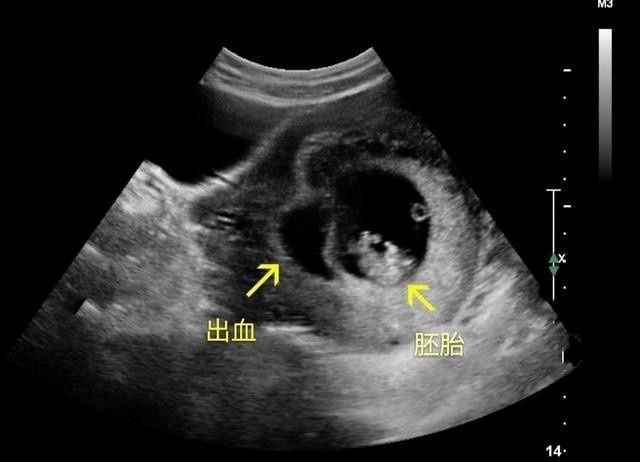

没任何表现的孕妈,就可以等到怀孕12周做产检时,一块儿再产检。

第一次早唐筛查,也就是NT检查,最佳检查时间是孕11-14周,而且需要提前预约,医生大多建议和怀孕12周的产检一块儿做。

这次检查是很重要的检查,孕妈们要提前预约好,并做好准备。

通过B超确定胎儿的实际孕周、检查胎儿的发育情况、看胎儿存在唐氏综合征的风险等。